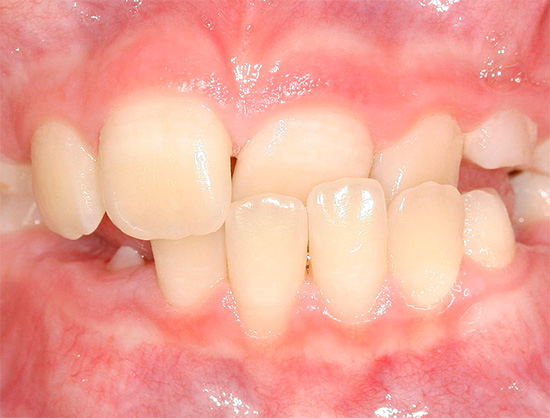

La foto mostra un esempio di un morso distale:

Nel morso distale si distinguono due sottoclassi, a seconda dell'inclinazione degli incisivi mascellari.